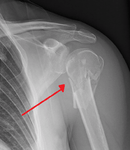

The upper or proximal extremity of the humerus consists of the bone's large rounded head joined to the body by a constricted portion called the neck, and two eminences, the greater and lesser tubercles.

The head (caput humeri), is nearly hemispherical in form. It is directed upward, medialward, and a little backward, and articulates with the glenoid cavity of the scapula to form the glenohumeral joint (shoulder joint). The circumference of its articular surface is slightly constricted and is termed the anatomical neck, in contradistinction to a constriction below the tubercles called the surgical neck which is frequently the seat of fracture. Fracture of the anatomical neck rarely occurs.[1] The diameter of the humeral head is generally larger in men than in women.

The anatomical neck (collum anatomicum) is obliquely directed, forming an obtuse angle with the body. It is best marked in the lower half of its circumference; in the upper half it is represented by a narrow groove separating the head from the tubercles. It affords attachment to the articular capsule of the shoulder-joint, and is perforated by numerous vascular foramina. Fracture of the anatomical neck rarely occurs.[1]

The surgical neck is a narrow area distal to the tubercles that is a common site of fracture. It makes contact with the axillary nerve and the posterior humeral circumflex artery.